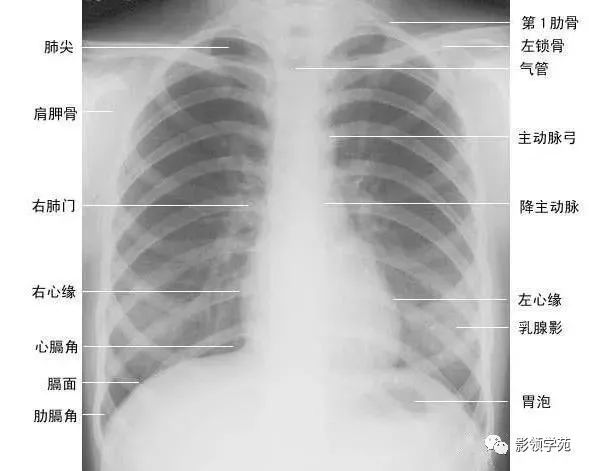

正常胸廓由软组织与骨骼组成,两侧对称(如下图)。

1、胸锁乳突肌及锁骨上皮肤皱褶 胸锁乳突肌起自胸骨柄及锁骨内端,向后上方斜行,止于乳突,在两肺尖内侧形成外缘锐利且较均匀的致密阴影。在胸骨头和锁骨头及锁骨之间形成一个小三角间隙,叫锁骨上窝或胸锁乳突肌间隙。当颈部偏斜时,两侧胸锁乳乳突肌阴影可不对称,勿误为肺尖部病变。锁骨上皮肤皱褶为与锁骨上缘平行的薄层软组织影,其厚度为3~5mm,内侧与胸锁乳突肌阴影相连,略成直角,系锁骨上皮肤及皮下组织的投影。

2、胸大肌起于锁骨的外侧分,胸骨和第1~6肋软骨,肌束行向外上方,至于肱骨大结节嵴。在肌肉发达的男性,于两肺中部的外侧形成扇形均匀致密影,下缘锐利呈斜行曲线,自肺野伸向腋部,与腋前皮肤皱褶相延续。

3、乳房及乳头 女性乳房于两下肺野形成半圆形的密度增高影,其下缘清楚,并向外与腋部皮肤连续,上缘不清,且密度自下而上逐渐变淡以至消失,其位置随年龄的增长而下垂,一般两侧对称。乳头在两下肺野相当于第5前肋间处形成边缘清楚的小圆形致密阴影,乳房越薄,乳头影境界越清晰,其特点亦为左右对称。青春期乳头呈半球状,约在第2~6肋之间。妊娠期乳腺可明显增大,至哺乳期结束后,乳房逐渐缩小,失去弹性而下垂,到老年期,乳房逐渐萎缩。